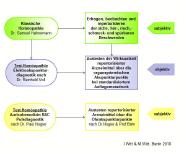

Allergien, Autoimmun-, Krebserkrankungen sind trotz angestrengter Bemühungen der konventionellen Medizin weiter im Vormarsch. Für viele der chronischen Erkrankungen (siehe Bild) gilt: die vernetzten Ursachen ihrer Entstehung unterliegen wissenschaftlich bis heute mehr der Vermutung, als dass sie bekannt sind. Während die sogenannte Schulmedizin überwiegend Beschwerdebilder auf der Basis statistisch selbstgenügsamer Studien behandelt oder unterdrückt, setzt die ANDERE MEDIZIN seit Jahrzehnten erfolgreich auf individuelle Regulationsdiagnostik und -therapie. Eine symptomen- kurierende, 'entweder-oder' Medizin kann nicht nur die Gesundung gefährden.

Diagnostik auf den Punkt gebracht

Akupunkturtestverfahren sind die Königsdisziplinen der komplementärmedizinischen Diagnostik: Elektroakupunktur nach Voll, Bioelektronische Funktionsdiagnostik nach Pflaum und der Vegetative Reflextest nach Schimmel. Jahrzehnte bevor Umweltmediziner Zusammenhänge zwischen Umweltbelastungen und Krankheiten entdeckten, lange bevor Schulmediziner Nobelpreise für Erkenntnisse bekamen, dass Viren Krebserkrankungen mit verursachen können, waren es mutige Ärzte, die trotz vehementen Widerstands der etablierten Medizin, über Akupunkturtestverfahren dies nachweisen konnten, publizierten und zu einer modernen, individualmedizinischen Diagnostik- und Therapiemethode verfeinerten. Wie gerade chronisch Erkrankte seit Jahrzehnten davon profitieren ... weiter